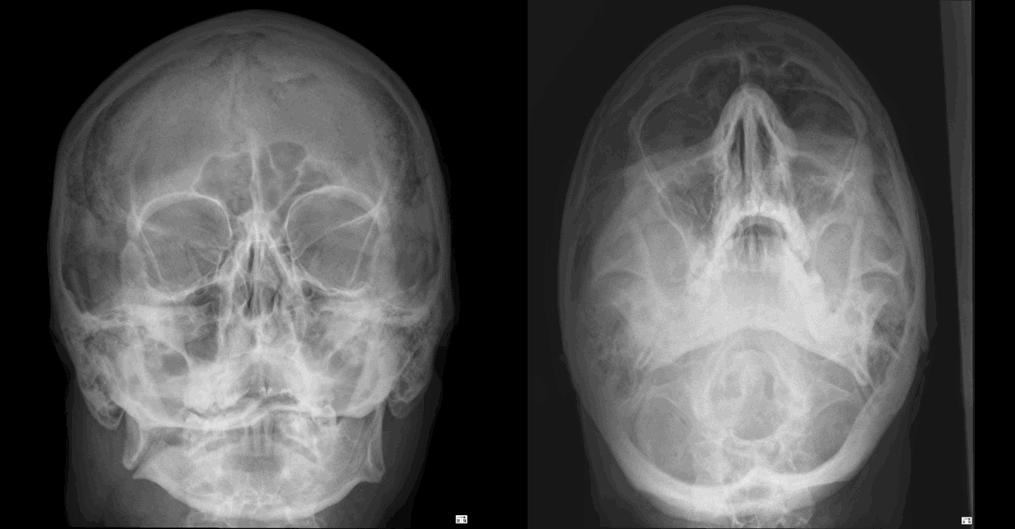

Age 31 male. Referral from ED. History: Post assault

Findings:

# angle right mandible

No temporomandibular joint (TMJ) dislocation

Management:

Urgent ENT/maxillofacial surgical referral

Consider facial CT with reconstructions

| Sample answer | Answer type | Explanation of scoring allocation |

|

Right angle of the mandible fracture Refer to max fax surgeon for further management |

High scoring answer |

This answer scored highly as the candidate observed the fracture and described the location accurately. They have also mentioned pertinent negative findings including no right TMJ dislocation. |

Acute fracture of the right mandibular angle Formal OPG/mandibular views to assess for further fracture. |

Mid scoring answer |

This answer has scored lower marks as the anatomical location of the right mandibular fracture has been omitted. CT of the brain, facial bones and cervical spine could be considered to be excessive in a young patient. |

Left inferior orbital rim fracture Referral to maxillofacial surgeons |

Low scoring answer |

This answer has scored low marks as the mandibular fracture was not mentioned and there is over-diagnosis of a left inferior orbital rim fracture. |